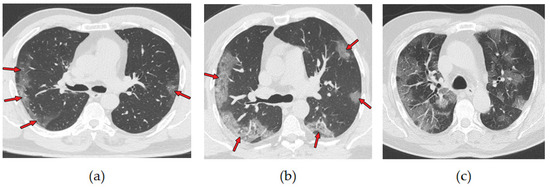

A chest CT scan combines data from multiple X-rays taken from different angles, which produces a detailed image of the lungs. CT scans are more effective than chest X-ray in early stages of COVID-19 disease detection. They have been used as a tool to diagnose and monitor the progression of the disease [9]. More than 70% of chest CT scans in patients with RT-PCR test-proven COVID-19 cases report ground-glass opacities, vascular enlargement, bilateral abnormalities, lower lobe involvement, and posterior predilection [10]. Figure 2 illustrates those abnormalities. Studies by [11,12] confirm that patients with COVID-19 pneumonia have ground-glass opacities in the earlier stages of the disease and pulmonary consolidation in later stages. Eventually, a rounded morphology and a peripheral pulmonary distribution are observed. Those abnormalities are analogous to those observed in other coronavirus infections, such as SARS-CoV-1 and MERS-CoV [13].

Figure 2. Axial nonenhanced chest CT images (lung window) in a 59-year-old man (a) and a 47-year-old man (b) show bilateral areas of ground-glass opacities (arrows) in a peripheral distribution; (c) shows bilateral ground-glass opacities and dilated segmental and subsegmental vessels, mainly on the right, in a 70-year-old man, each with positive RT-PCR test results for SARS-CoV-2. Adapted from [10].